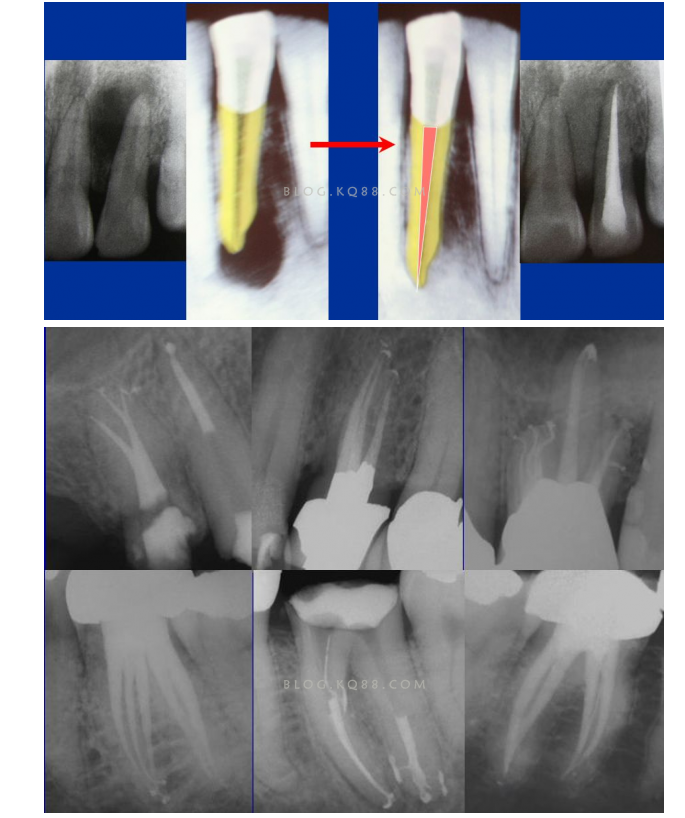

1簡(jiǎn)化難度 一個(gè)牙齒的根管治療難易程度不單單是根管的彎曲、細(xì)小、牙位、是否再治療決定的,開(kāi)髓的直線(xiàn)進(jìn)入和根管口的預(yù)先恰當(dāng)處理可以簡(jiǎn)化很大的難度,開(kāi)髓是根管成敗的基礎(chǔ)。對(duì)于彎曲根管冠部的直線(xiàn)入口就顯得尤為重要,冠部良好的直線(xiàn)入口可以避免側(cè)穿、臺(tái)階、遺漏根管等問(wèn)題的發(fā)生,冠部直線(xiàn)入口形成的良好情況,取決于醫(yī)生的理念和合理的器械選擇。開(kāi)髓孔的大小不是由醫(yī)生和患者的意愿決定的,而是由要治療牙齒的髓腔大小決定的。

2相信有更多的根管存在 相信根管的數(shù)目比我們想象的多,根管系統(tǒng)的復(fù)雜程度比我們想象的見(jiàn)到的要更復(fù)雜,我們只有用盡所有努力和辦法才可能達(dá)到預(yù)期目標(biāo),對(duì)于上 牙合 6的MB2來(lái)說(shuō)過(guò)去是偶爾有,現(xiàn)在是偶爾沒(méi)有,各種文獻(xiàn)報(bào)道的比例也不一致,我在培訓(xùn)班醫(yī)生帶來(lái)的離體牙中幾乎沒(méi)有見(jiàn)到?jīng)]有的,臨床中也是一樣。對(duì)于尋找的方法來(lái)說(shuō),我覺(jué)得相信有才是最重要的,首先相信一定有就會(huì)想各種辦法,找到的幾率就會(huì)更多。如果有條件在顯微鏡和超聲的配合下效率會(huì)更高。